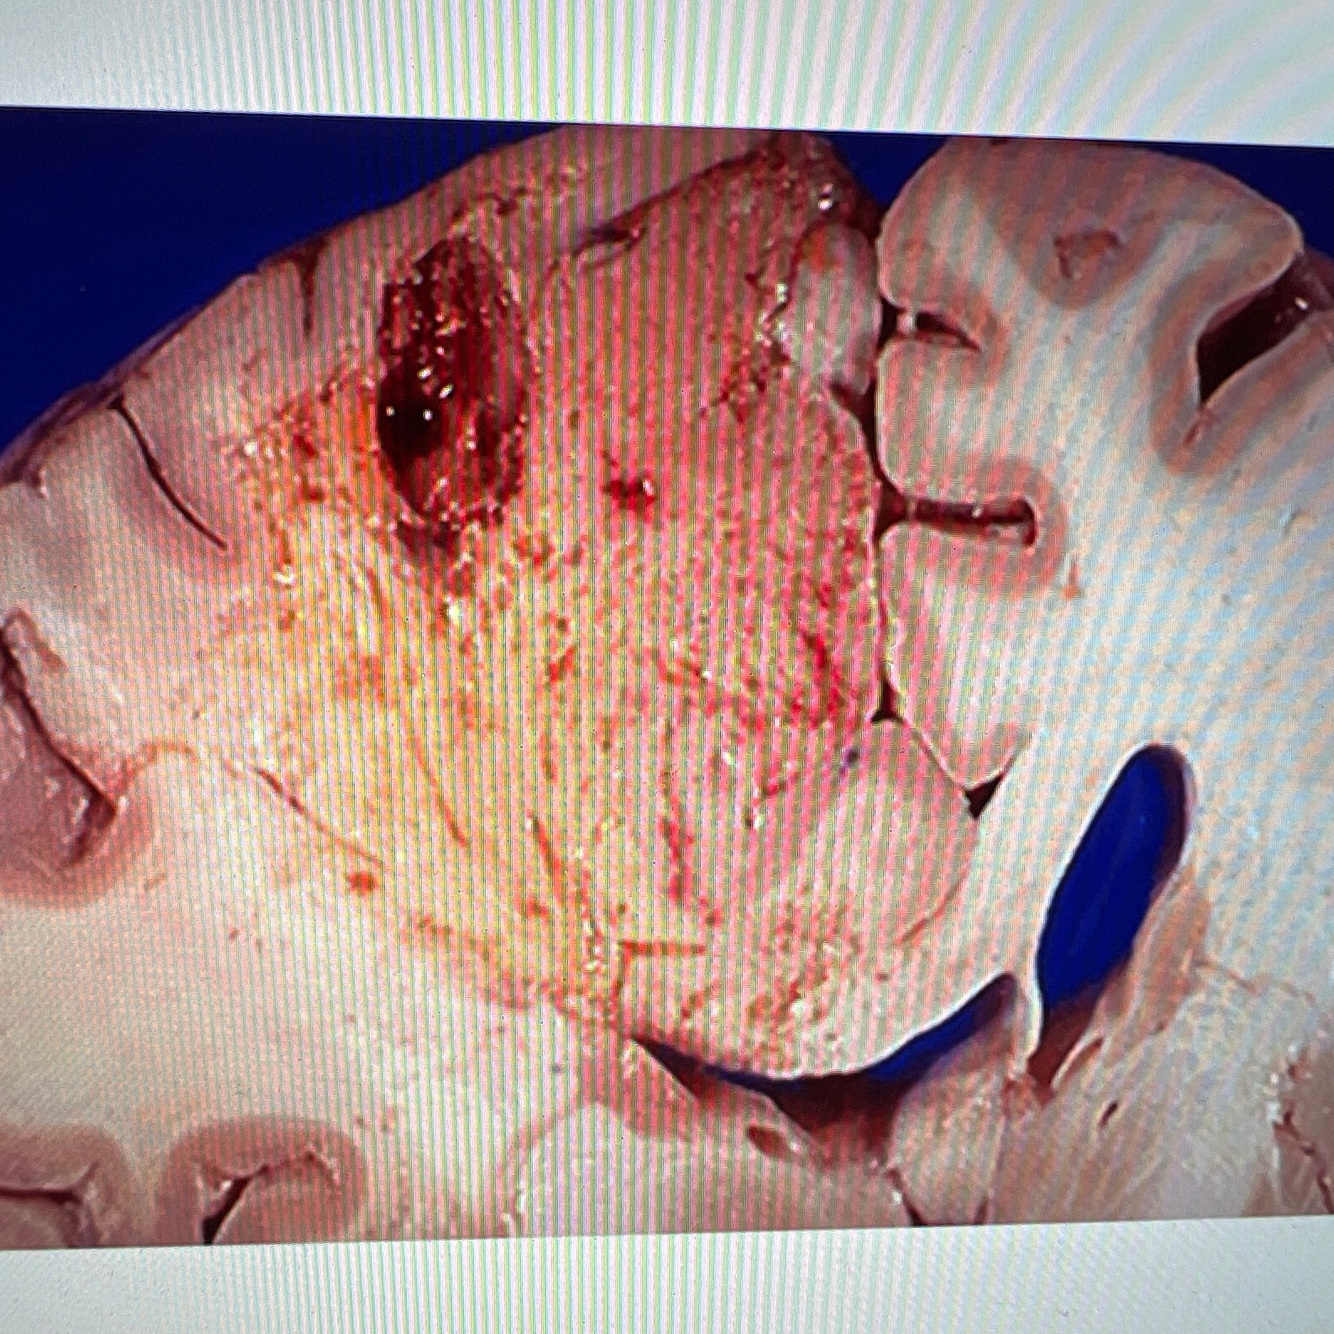

Diagnosis: brain abscess

Location: cerebrum

A coronal section in the brain shows a cavity in the left cerebral hemisphere having a thick wall and lined by yellowish purulent exudate

The lateral ventricle is compressed due to mass effect